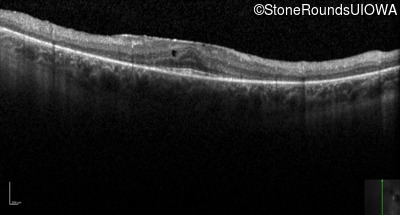

Optical Coherence Tomography - Right - 20/25 -2

Exemplar / OCT Stack